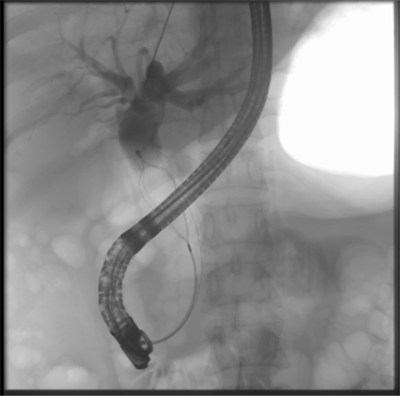

【39健康网】胆管“卡”石头? 消化内科专家25分钟完成ERCP取石术